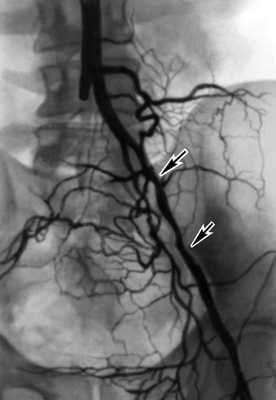

Топическую картину поражения можно установить с помощью ангиографии радионуклидной (Ангиография радионуклидная), дигитальной субтракционной и рентгеноконтрастной ангиографии. Из методов рентгеноконтрастного исследования предпочтение отдают транслюмбальной пункционной аортографии, при которой можно получить изображение не только аорты, но и дистального сосудистого русла конечностей. С помощью аортографии выявляют локализацию и протяженность поражения (рис. 2).

Рис. 2. Аортограмма больного с синдромом Лериша, обусловленном атеросклеротическим поражением бифуркации аорты и общих подвздошных артерий: окклюзия правой общей подвздошной артерии, участки стенозирования левой наружной подвздошной артерии указаны стрелками.